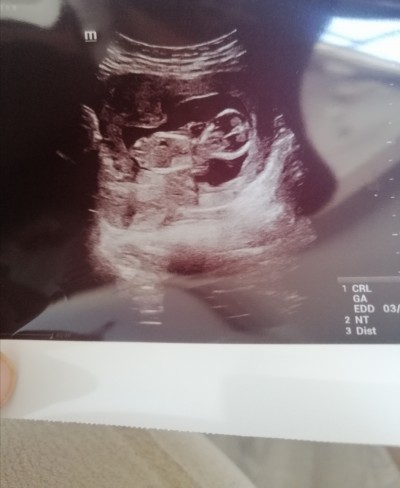

Merhaba kızlar ultrason fotoğrafına ya da Nub a göre cinsiyet tahmini yapabilir misiniz. Tecrübeli anneler merakla bekliyorum :)

Gebelik haftası 12 haftalık

nubu goruyor musun acisina bak duz, dik degil

Erkek gibi bnce erkek diyom ben